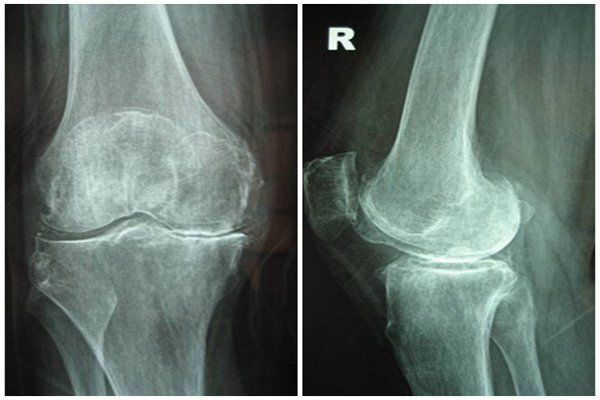

5.3 Thoái hóa khớp

Trên hình ảnh X-quang có thể hình thấy hình ảnh gai xương ở vùng đầu xương, dày đậm xương dưới sụn, hẹp khe khớp và có thể hình thấy một số khuyết xương nhỏ ở đầu xương.

5.4 Bệnh Gout

Hình ảnh điển hình trong bệnh Gout là hẹp khe khớp, gai xương ở đầu xương và các ổ khuyết hình tròn hoặc bầu dục ở giữa hoặc phía trên cạnh đầu xương.